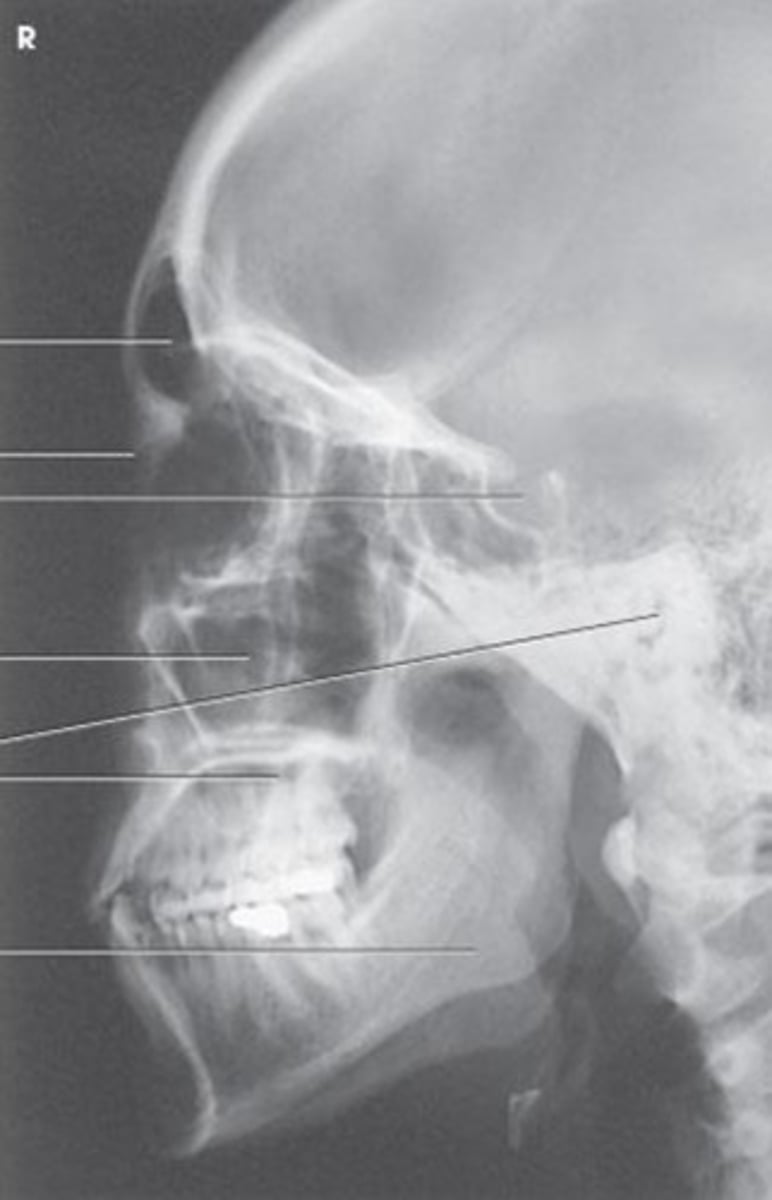

Lateral Facial Bones

Name